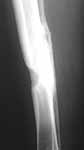

This patient is a 40 year old woman who is five years status post an open tibia fracture. She has healed her tibia, but has developed a chronic osteomyelitis w/ MRSA. She has had several debridements. She's had labeling, with Tetracycline with the debridement ((Dahners JOT)) as well as reaming of her tibia and placement of local antibiotic beads to try and clear the osteomylelitis as well as systemic IV antibiotics. She appeared to heal but recently has had a recurrence with a small pinpoint drainage on the antermedial aspect of her tibia. A CT scan has not been helpful in identifying a nidus of persistent bony infection. She complains of pain that coincides w/ her fluctuating drainage. Any ideas?